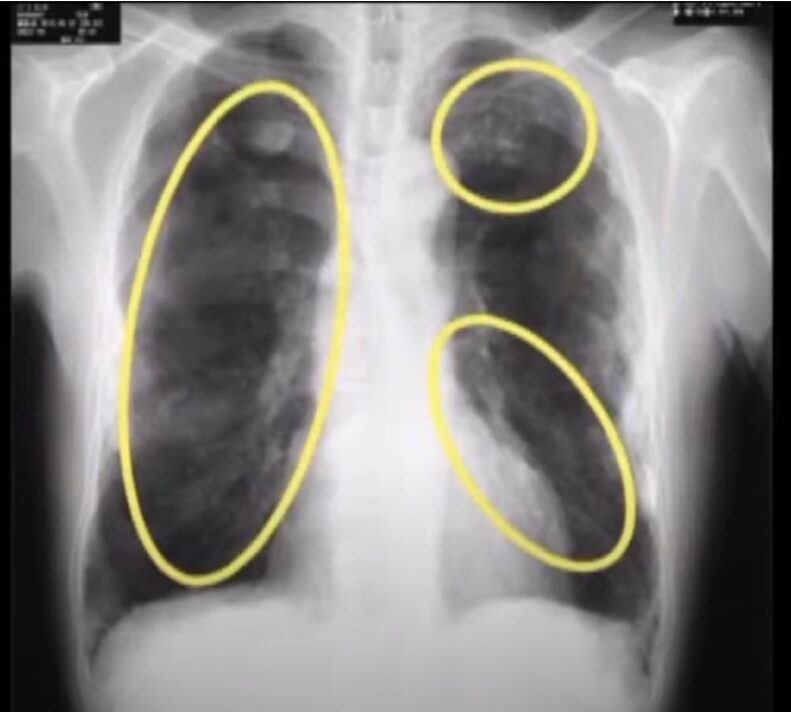

しかしながら吸入するとそれらの性質が人体に有害作用を及ぼすことがわかってきています。